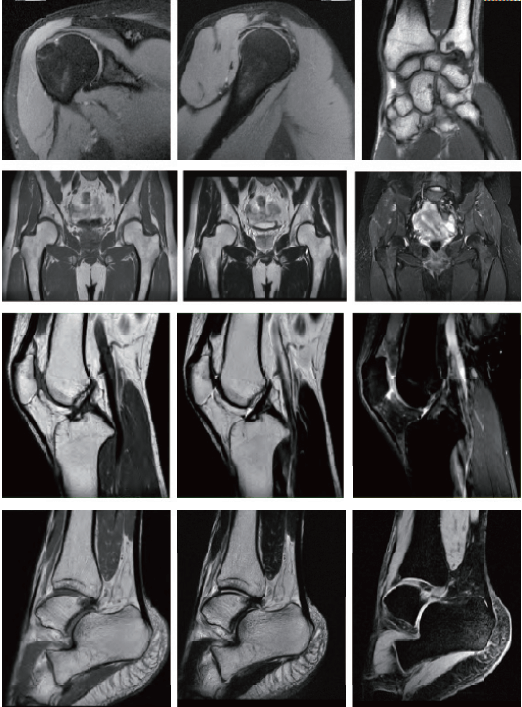

臨床畫廊